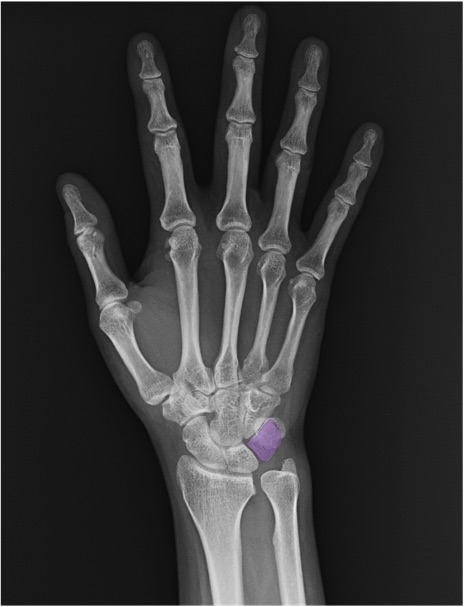

三角骨(triquetrum)の手関節レントゲン画像における正常解剖

舟状骨(scaphoid)

月状骨(lunate)

中手骨(metacarpal bone)

基節骨(proximal phalanx)

中節骨(middle phalanx)

末節骨(distal phalanx)

橈骨(radius)

尺骨(ulna)

尺骨茎状突起(ulnar styloid process)

CM関節(carpometacarpal joint)

IP関節(interphalangeal joint)

MP関節(metacarpophalangeal joint)

PIP関節(proximal interphalangeal joint)

DIP関節(distal interphalangeal joint)